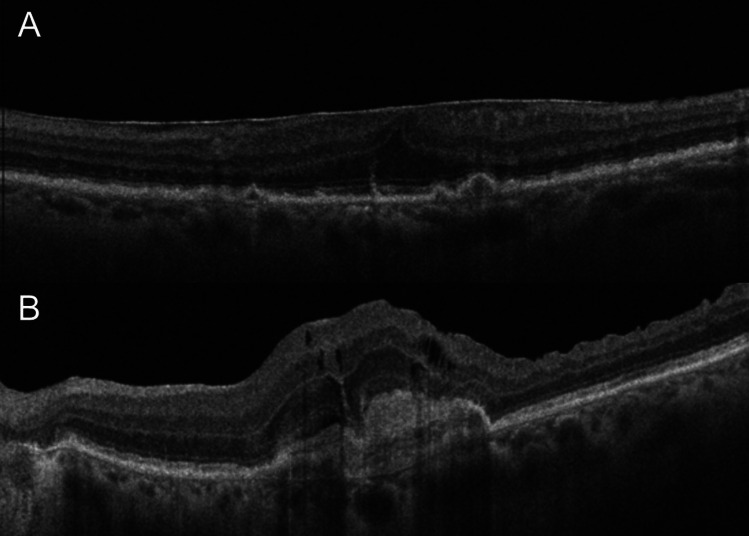

Abstract Image